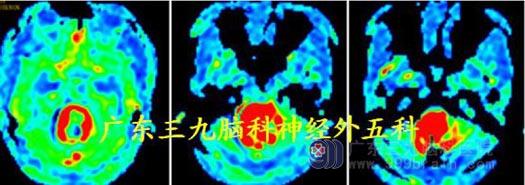

MR 灌注测值395.61±232.75ml/100g/min;提示病灶高灌注,血供极其丰富。

头颅MR:左侧小脑半球仍示一大囊小结节病灶,实性部分为两个小结节,左侧小脑半球病灶实性部分呈明显高灌注,感兴趣区CBF 测值为191.54ml/100g/min。